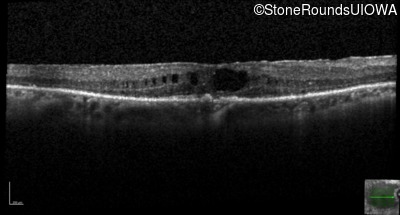

Age at visit: 66 years

OD OS